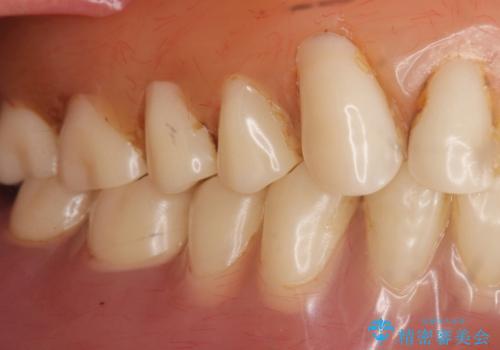

「ぴったりしていて全然はずれません!」と喜んで下さいました。

古い入れ歯は人工歯がすり減っており左右均等に咬むことができなかったそうですが、新しい入れ歯だと両側でしっかり咬むことができるとご満足頂けました。